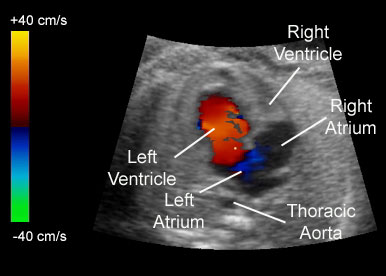

در این روش امواج فراصوت به بدن ارسال میشوند و پس از برخورد با گلبولهای خونی بازتاب مییابند؛ دستگاه با تحلیل این بازتابها، وضعیت جریان خون را به صورت رنگی (معمولاً قرمز و آبی بر اساس جهت و سرعت) نشان میدهد. این قابلیت، ارزیابی سریع هرگونه انسداد، لخته یا ناهنجاری عروقی را ممکن میسازد.